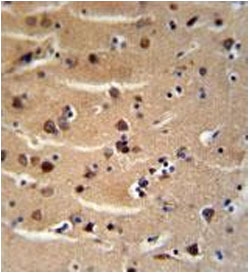

AXIN2 antibody immunohistochemistry analysis in formalin fixed and paraffin embedded human brain tissue

IHC (Paraffin) : 1:50-1:100